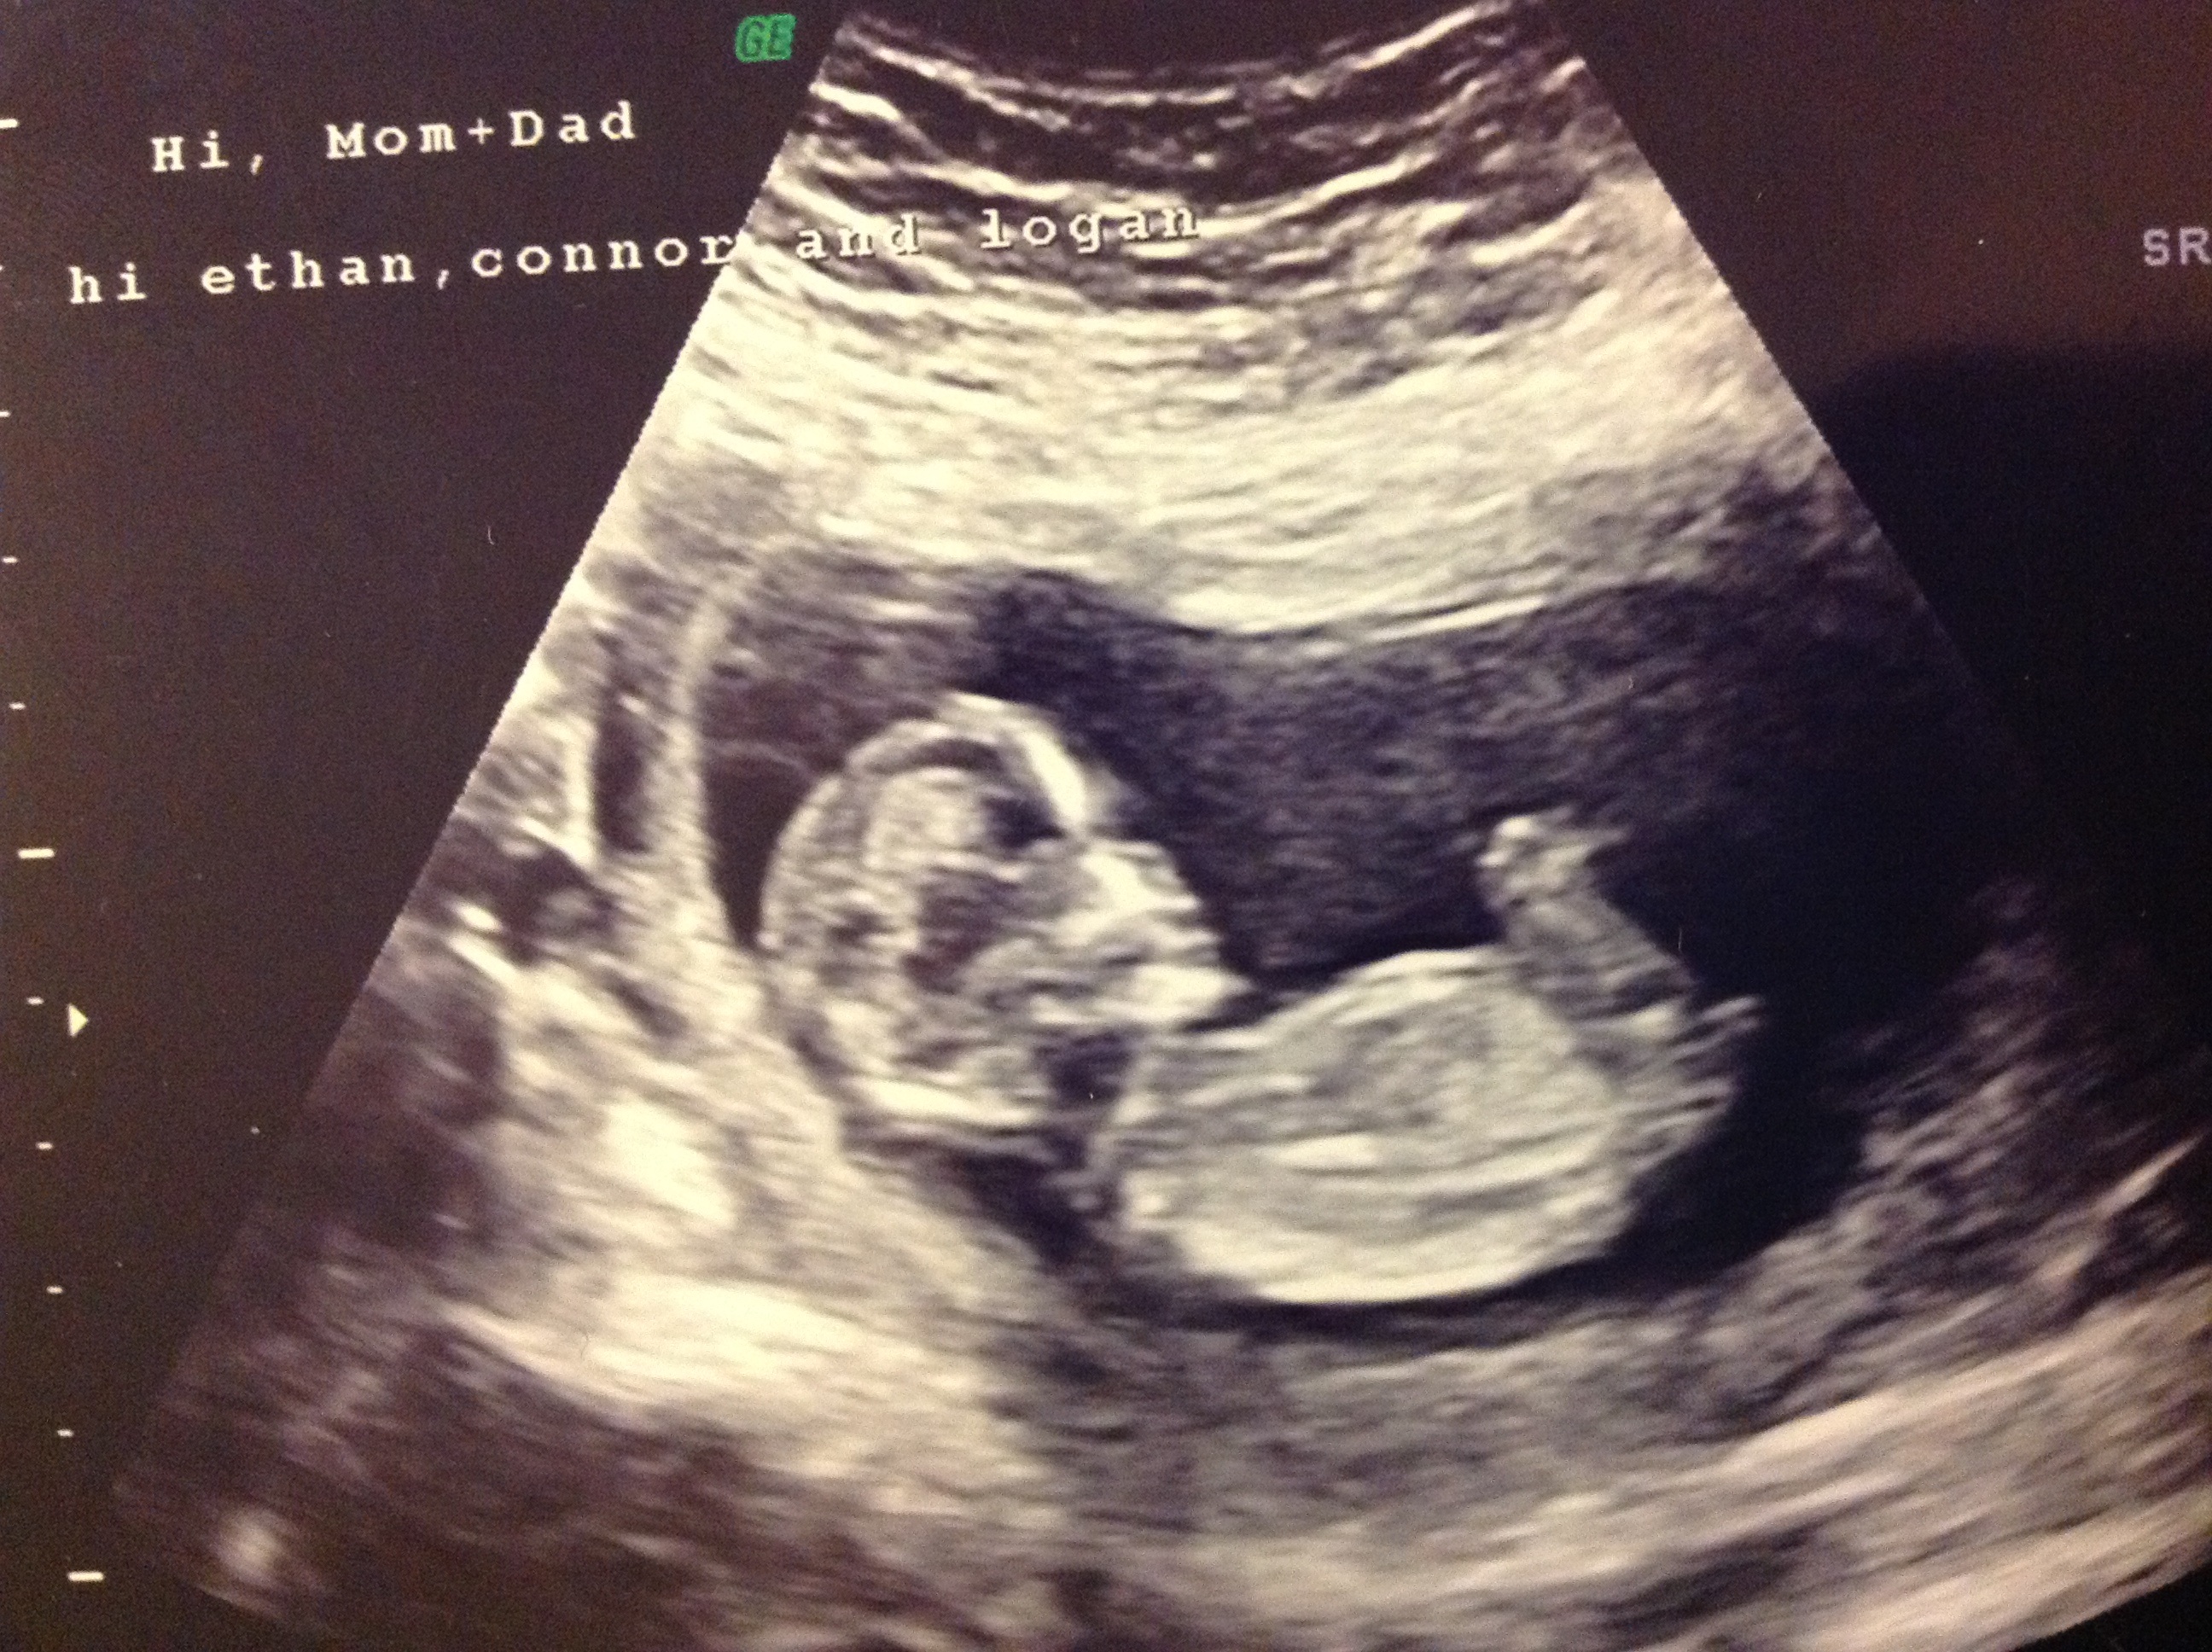

Had our 12 week ultrasound today!!

After 12 weeks, its accuracy goes down. Gender detect by us after 33 weeks in position of placenta posterior upper segementt grade ii maturity.heart beat 149.in 26 week us report. Check out my designer online children's. Had our 12 week ultrasound today!! Interesting to note, the doppler actually has higher levels of. 11 week scan any gender guesses. This question doesn't have a straight forward answer. Gender confirmed by harmony test! 12 week ultrasound for gender reveal. A 2016 study looked at the accuracy of such tests. See more ideas about ultrasound gender, ultrasound, gender prediction. You had an ultrasound and the ultrasound sonographer told you that they're suspicious of a boy. The 12 weeks ultrasound examination can be done from 11 weeks 4 days to 13 weeks 6 days.